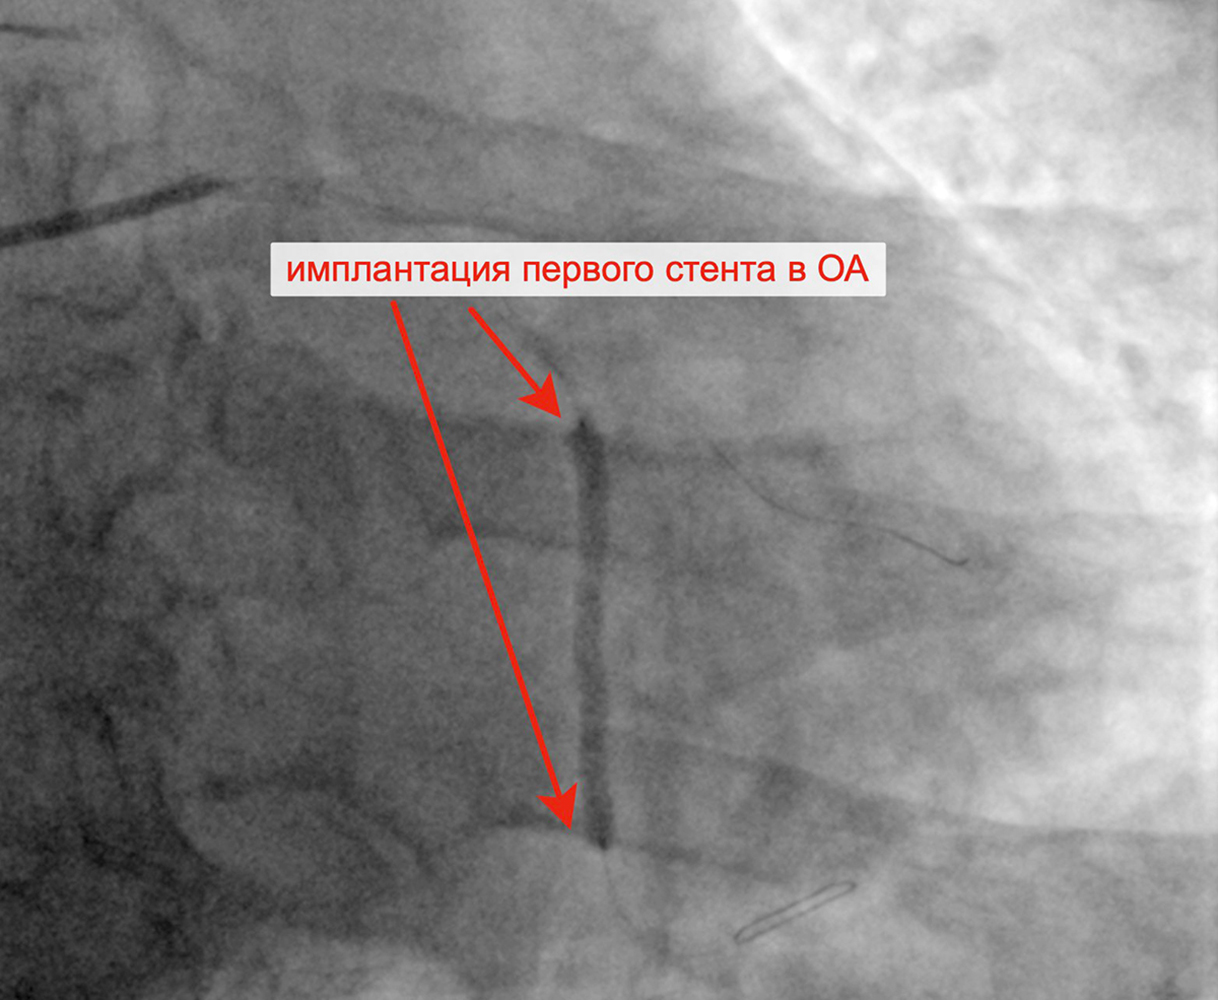

В марте 2023 г. в связи сохраняющейся одышкой, загрудинными болями при физической нагрузке пациент госпитализирован в кардиологическое отделение для решения вопроса о проведении следующего, третьего этапа реваскуляризации. Учитывая наличие ангинозных болей, результаты проведенных обследований (положительным стрессЭХО), коронарографии, наличие гемодинамически значимых стенозов коронарных артерий, принято решение о проведении баллонной ангиопластики и стентирования огибающей артерии (2 стента с лекарственным покрытием). Контрольная ангиография после успешного чрескожного коронарного вмешательства: стенты и ОА с ветвями проходимы, позиционирование стентов адекватное, диссекции или остаточного стеноза в стентированном сегменте ОА нет, кровоток TIMI 3 по ОА и всем ветвям.

Критические стенозы ОА Заведены проводники в ОА и ВТК

Имплантация первого стента в ОА Имплантация второго стента в ОА

Финальный результат имплантации 2 стентов в ОА